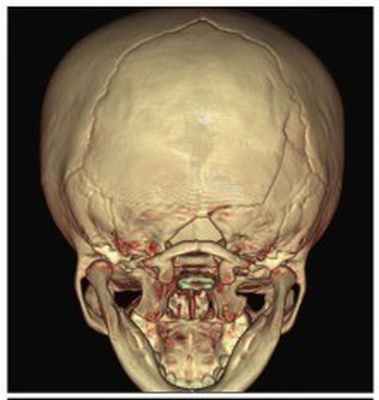

Рис. №2 а) – вариант нормы

б) – деформация черепа вызванная синостозом (слиянием) лямбдовидного шва слева, указателем показаны множественные пальцевые вдавления (истончение костной ткани, вплоть до появление «дыр»).